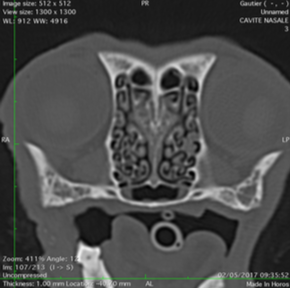

Les scanners du nez

Le scanner est l'examen de choix pour une exploration nasale complète... La cavité nasale de nos carnivore est formée de nombreux plis de muqueuses, appelés volutes, qui vont permettre un odorat très développé. Les lésions ne sont pas rareset se repartissent de la manière suivnte:

Scanner Normaux

Scanners nasaux anormaux